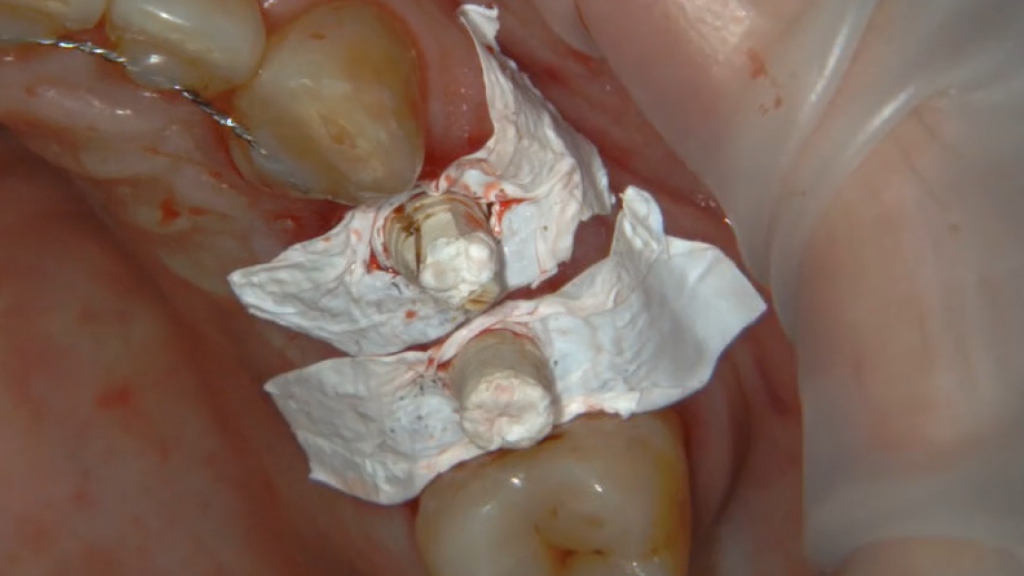

Одномоментная имплантация Impro с установкой временного абатмента

Описание клинического случая:

• Атравматичное удаление зуба 2.4, 2.5

• Одномоментная дентальная имплантация IMPRO

• Использование фибриновой мембраны Clot-PRF

• Установка временного абатмента IMPRO

• Изготовление индивидуального формирователя десны

Клинический случай Узденовой Зульфы Альбертовны